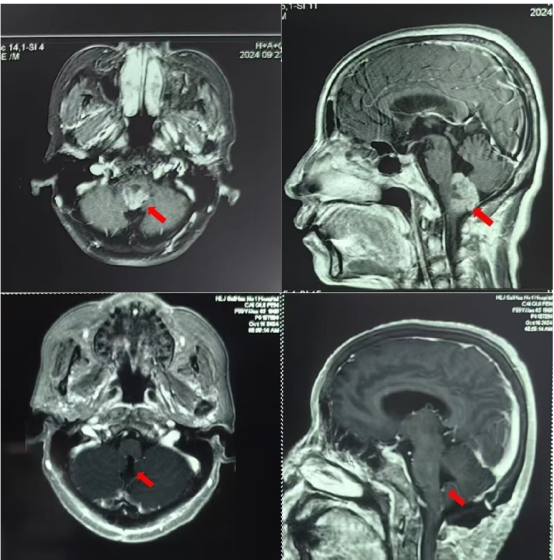

韩大勇教授结合患者病史和影像学检查确诊为延髓胶质瘤。延髓是脑干的重要组成部分之一,是人体的生命中枢,控制人体的呼吸和心跳等重要的生命活动,曾一度被认为是手术禁区,患者肿瘤较大,与延髓间界限不清晰,术后有呼吸功能障碍风险,手术难度较大。

韩大勇教授邀请杨光主任及科室专家组成员联合会诊,根据术前检查详细评估患者状态、肿瘤特点,为蔡女士制定了最佳的手术方案和术后救治方案,经过充分准备后韩大勇教授带领鲁恩州、朱延伟医生为患者实施了精准手术治疗,术中在处理延髓肿瘤生发部位时患者出现血压飙升和心率跳崖式减慢,在麻醉科刘洋医生和手术室护士长带领的团队全力配合下最终顺利为患者完整地切除鸡蛋大小的延髓肿瘤。术后病房护理团队为患者制定个性化护理方案,患者一周后顺利出院。